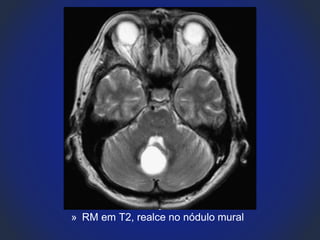

» RM em T2, realce no nódulo mural